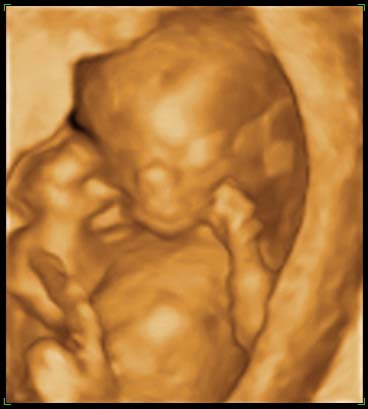

A Three-Month(!) Old Baby in the Safety of Her Mother's Womb